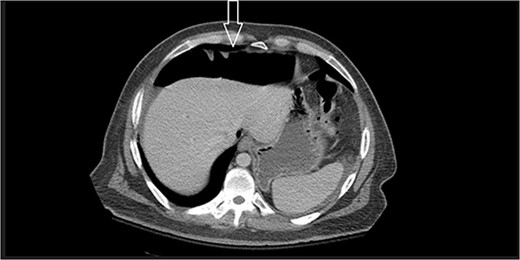

Eleven days post-discharge, he presented to the ER with the same symptoms. CT once again demonstrated pneumoperitoneum (see Fig. 3). Perforated hollow viscus structure is suspected; however, no rim-enhancing abscess is evident. Given his previous two negative ex-laps, a repeat EL was deferred. A conservative treatment plan of pneumoperitoneum was implemented for IP.

Amount of pneumoperitoneum increased compared with previous CTs.